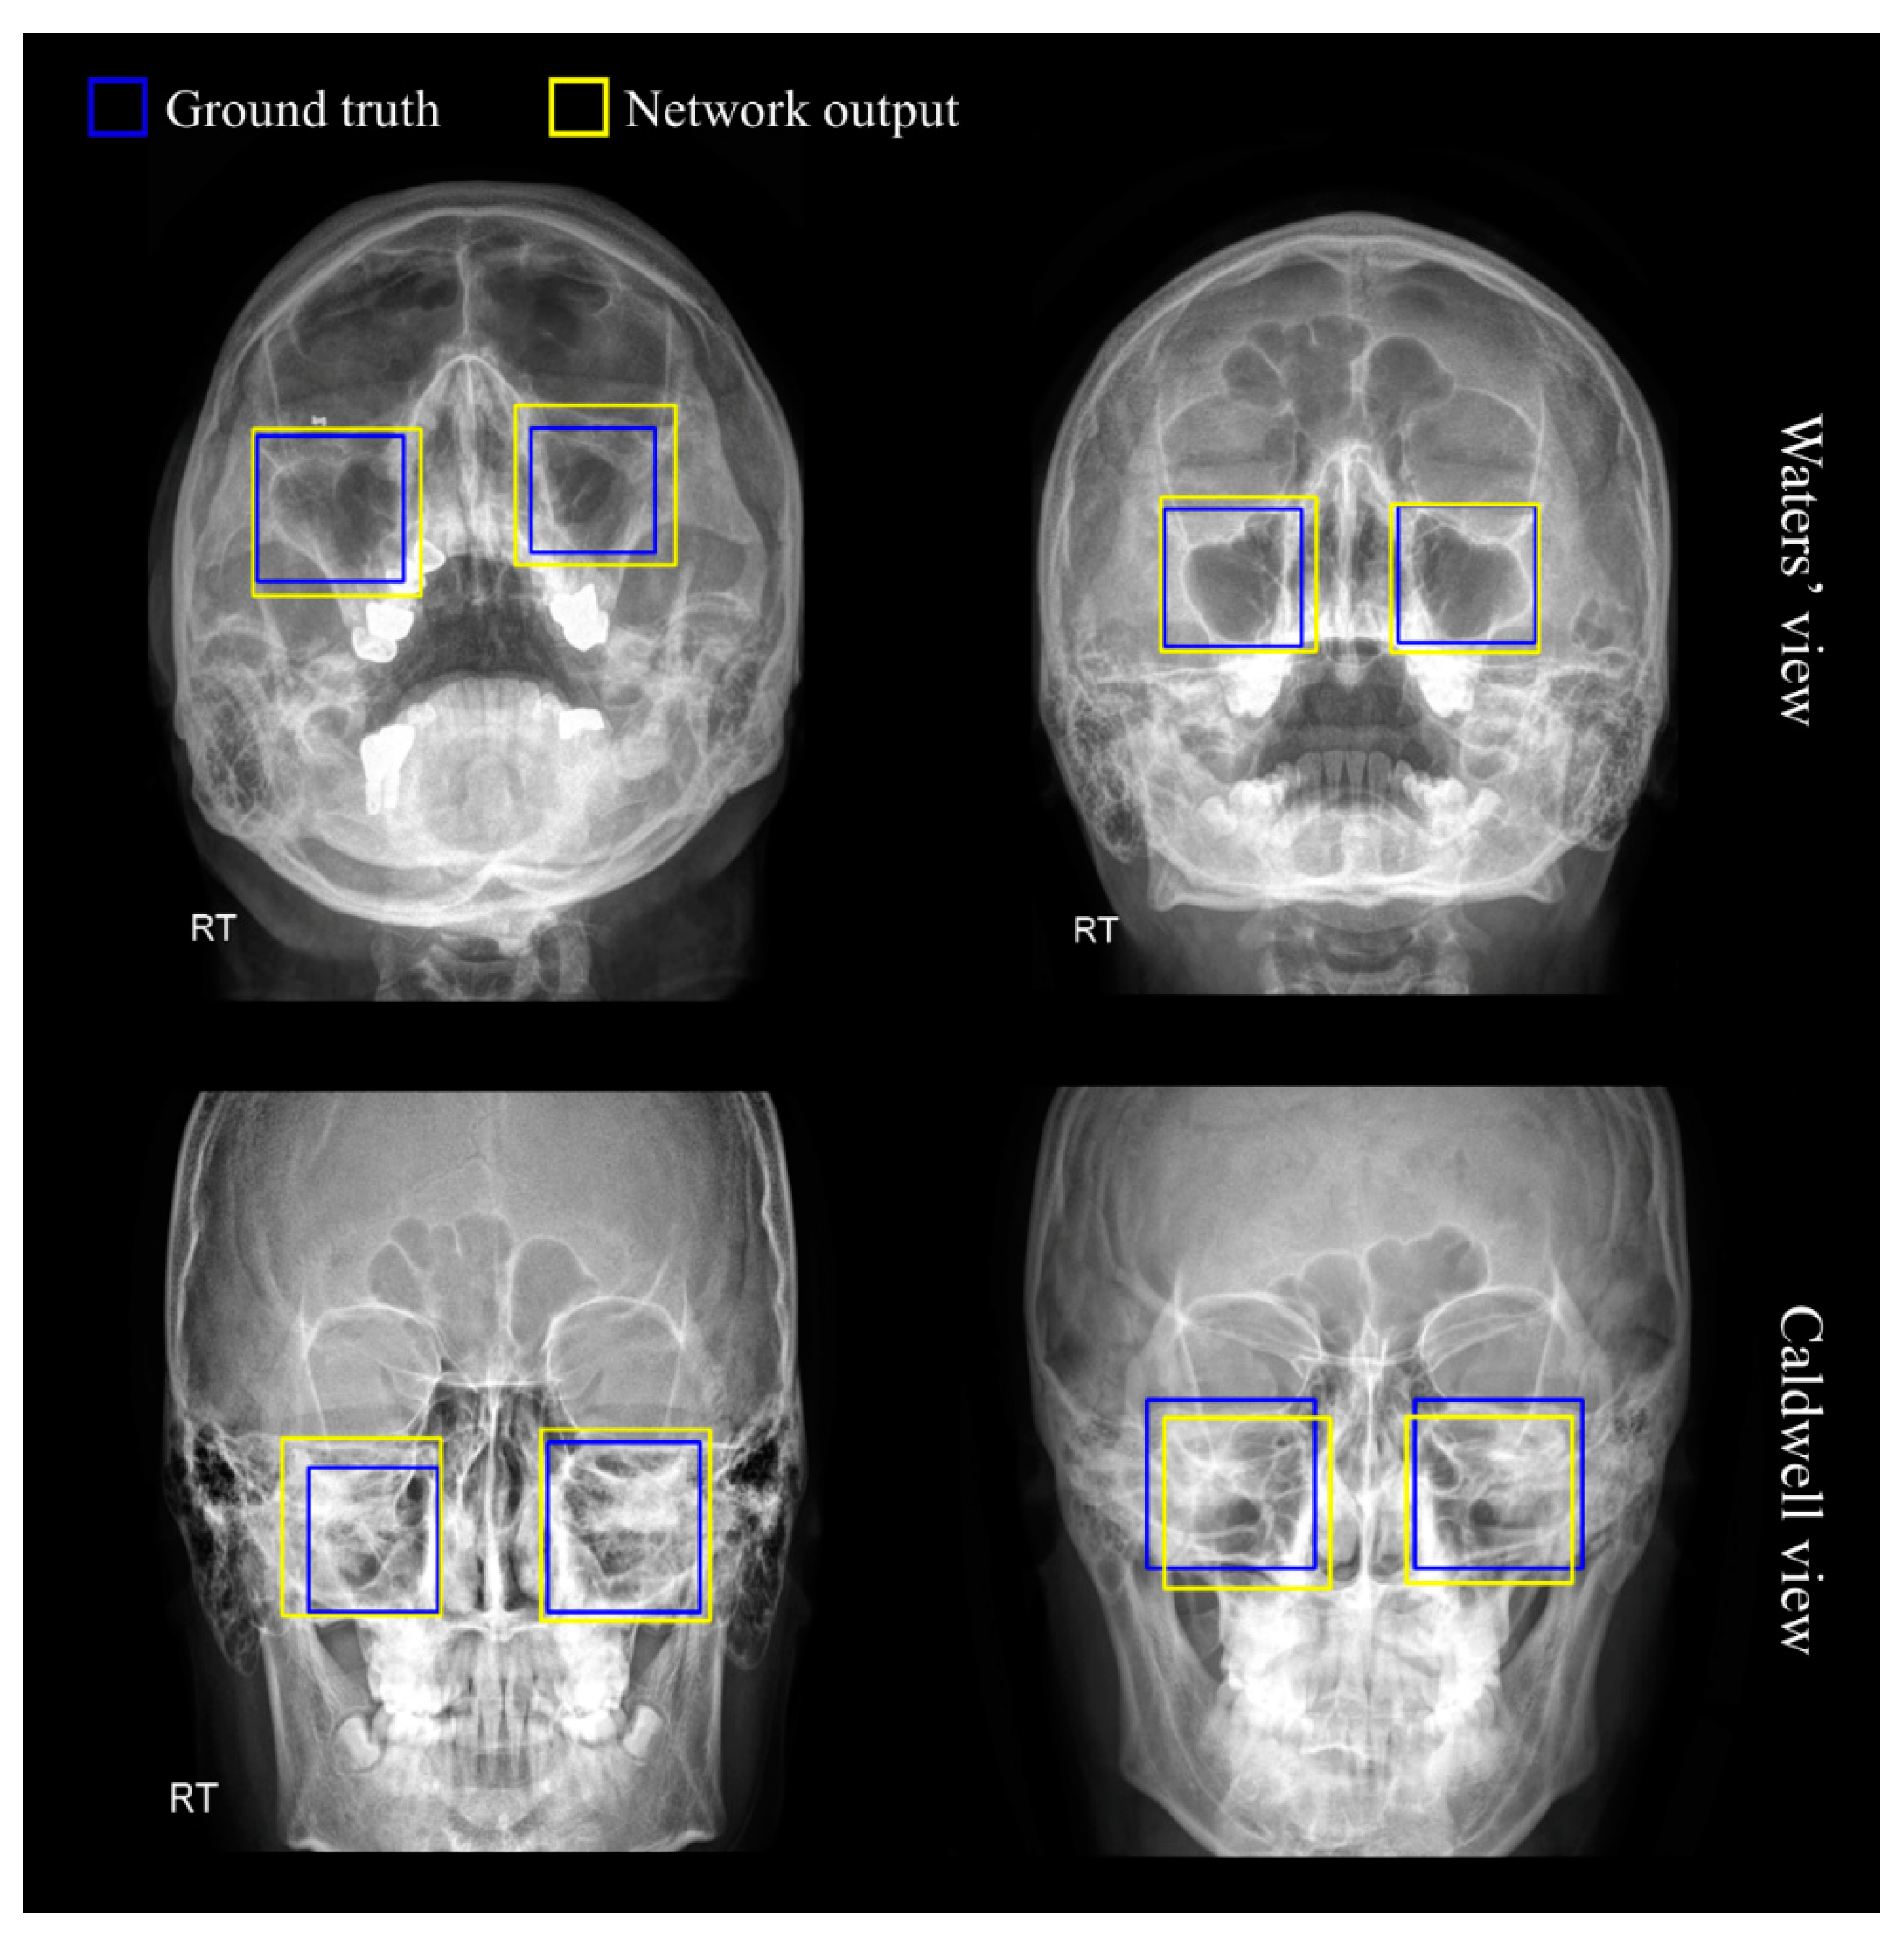

Diagnostics Free FullText Auxiliary ClassifierBased Watters X Ray Although the parietoacanthial projection (waters method) is widely used, many institutions modify the projection by radiographing the patient using less extension of the patient’s neck. Orbital fissures like blow out and. this case is an example of a normal orbits series comprising of the waters (om0°) and lateral views. hello everyone.the topic is waters view which is also. Watters X Ray.